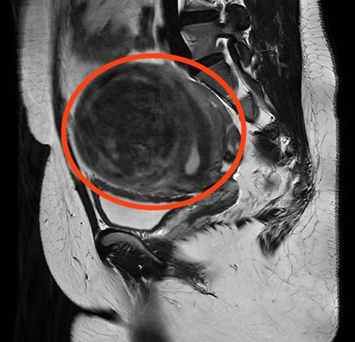

CT检查显示子宫左侧壁巨大肌瘤

“2年前,肌瘤开始明显增大,今年频繁出现尿频、尿急症状,严重影响了日常生活。”曹女士介绍,为寻求进一步治疗,她来到立博体育 妇科门诊就诊。经过B超检查显示,曹女士子宫左侧壁肌瘤内可见102*88*92mm的包块,考虑为子宫肌瘤。面对如此“巨大”的肌瘤,曹女士忧心忡忡,以为只有通过开腹手术才能将其切除,手术过程及术后遗留的疤痕让她既害怕又焦虑。